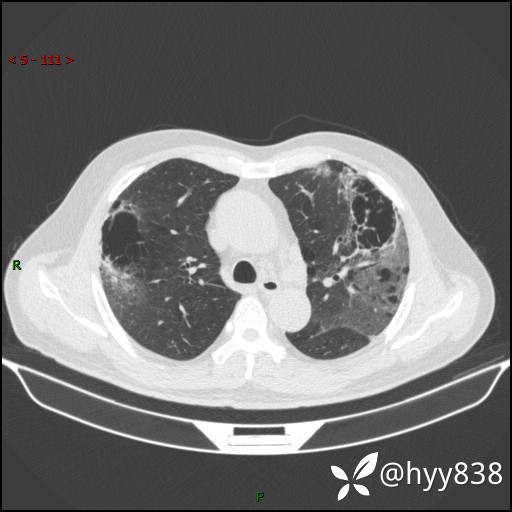

一周后胸部CT